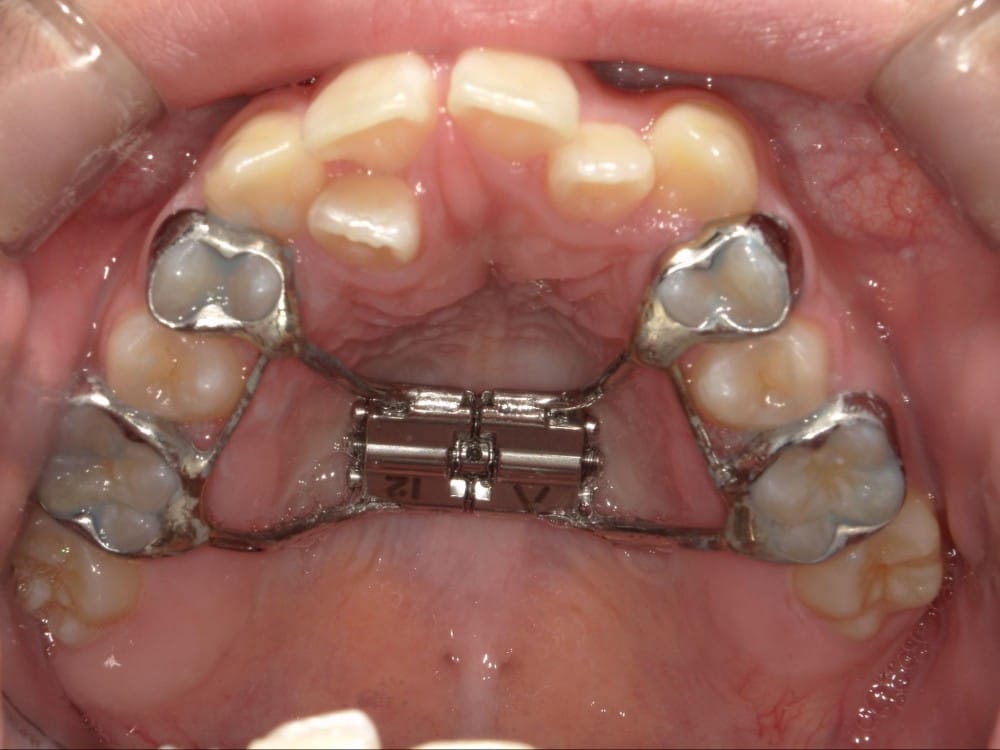

② セファロ(横顔レントゲン)分析

骨格的な問題があるかどうかを数値で評価します。

上顎・下顎の前後関係、前歯の傾斜角度、口元の軟組織のバランスなどを客観的に確認することで、「歯が原因なのか」「骨格が原因なのか」を明確にします。

- セファロによる骨格診断